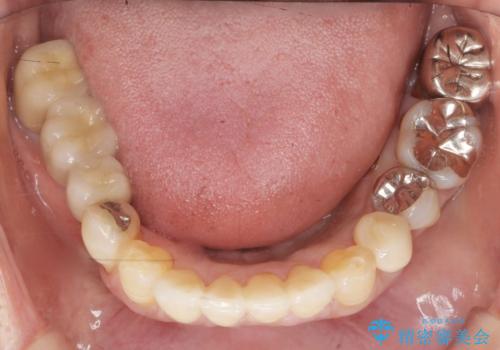

- 上の奥歯がないまま長年過ごしていたら前歯もぐらぐらしてきてしまったことを主訴に来院された患者様です。

奥歯の咬み合わせがないことにより前歯に負担がかかり動揺が出ていました。

精査したところ右下の奥歯も歯周病により保存不可能な状態でした。

なるべく予算を抑えたいとのご希望から、上顎は入れ歯、右下臼歯部はインプラントによる治療を行いました。

上の前歯は動揺を抑え、入れ歯の着脱にも耐えうるように被せ物を連結させることにしました。